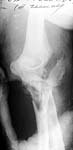

The olecranon is certainly comminuted, but if the wound is small all the pieces should be there. I would favor an attempt at ORIF w/ plating to reconstruct as much as possible. He is a young laborer and should have good bone quality.

The attached case was similar, but not quite as comminuted.

Injury: